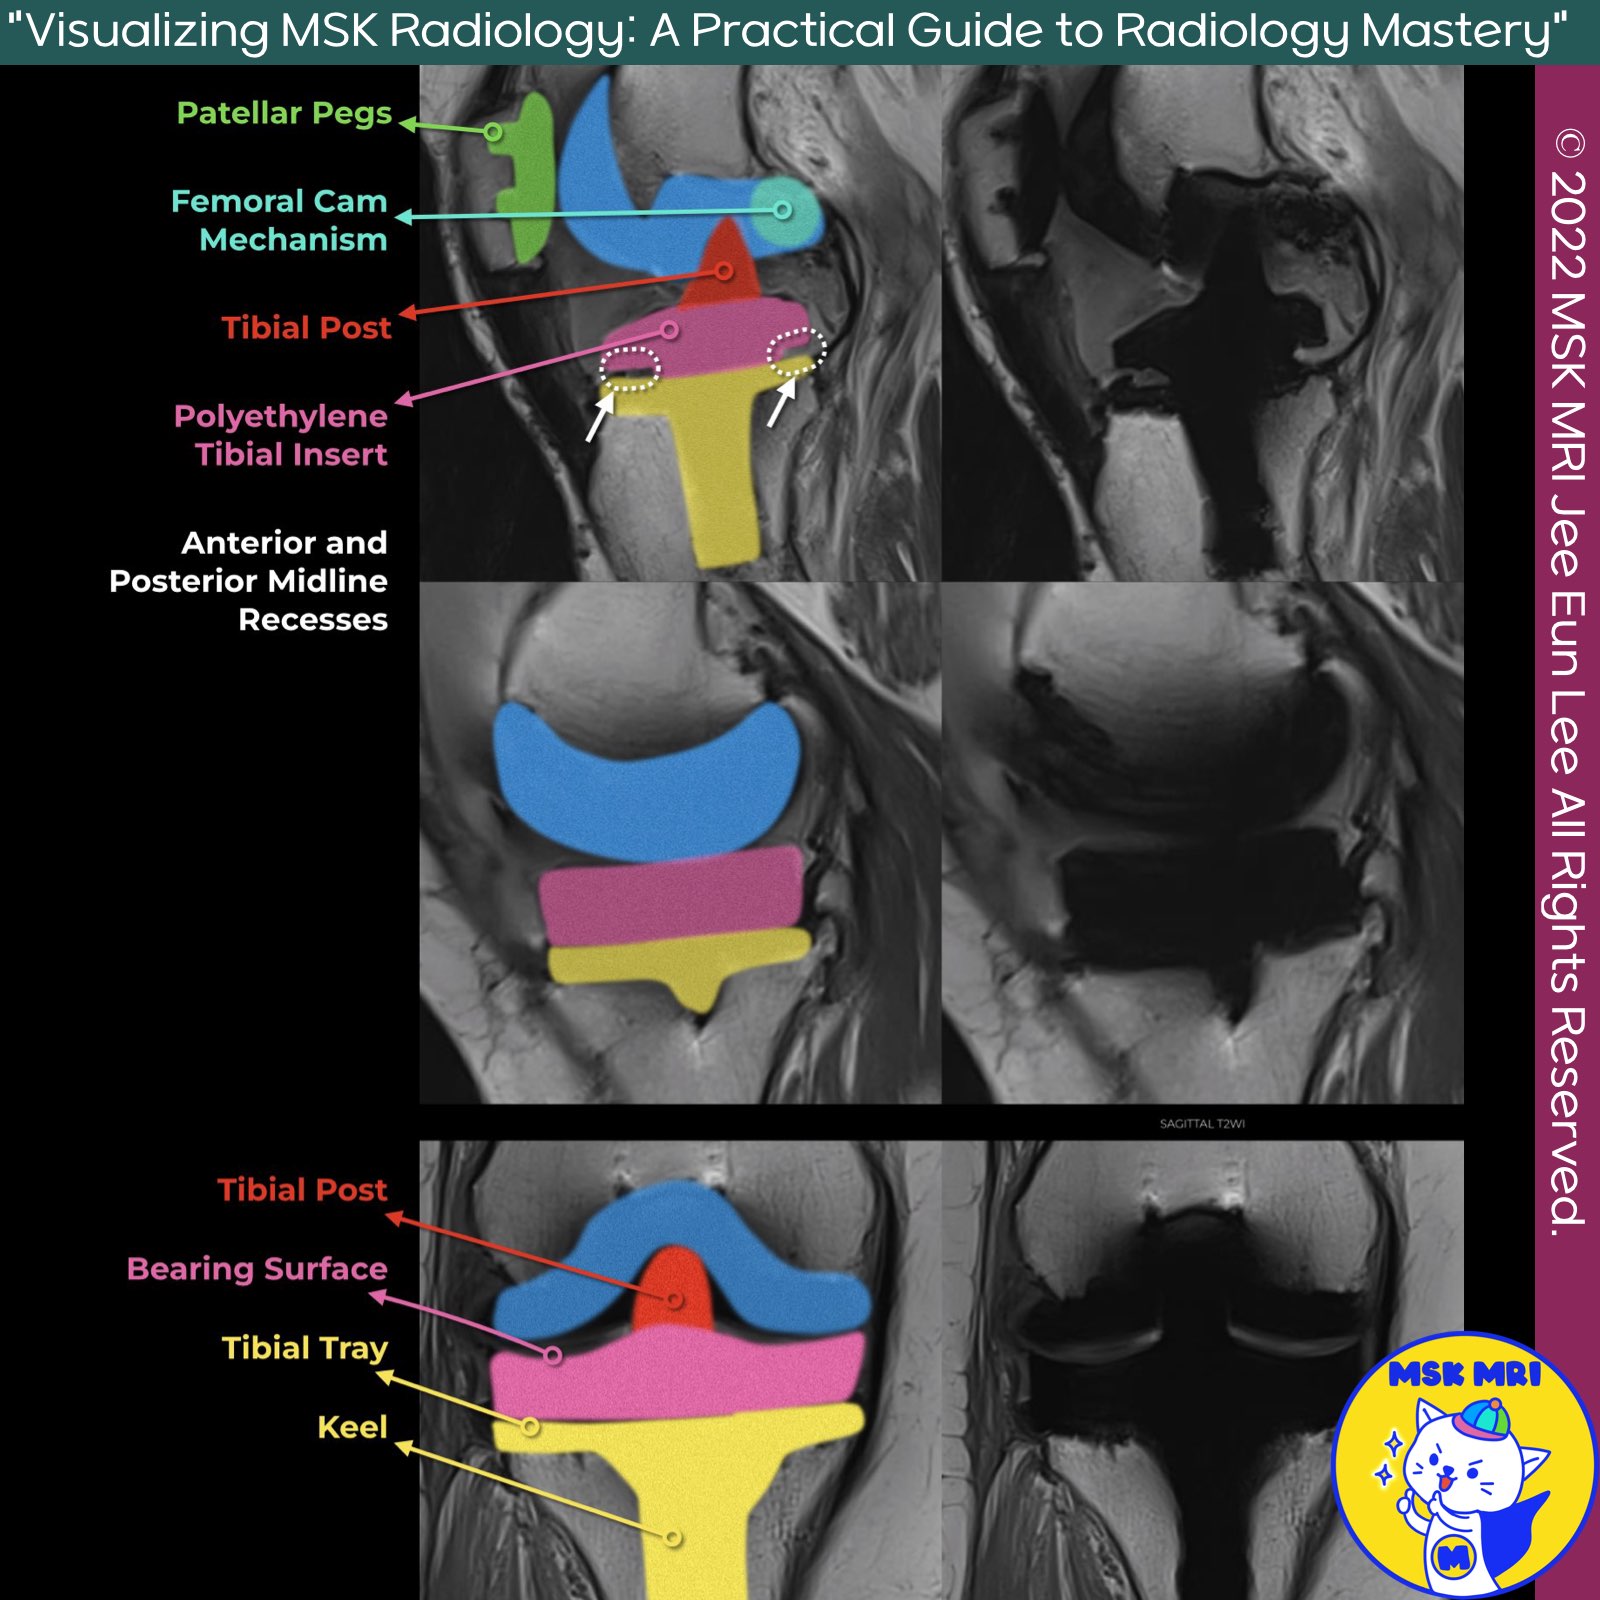

📌 MRI Evaluation of PS Knee Prosthesis

✅ Axial Images

- Axial images are most useful for evaluating the bone-implant interface around the patellar and tibial components.

- Additionally, axial images demonstrate the synovial lining, a popliteal cyst, the semimembranosus tendon, and the neurovascular structures about the knee.

✅ Sagittal Images

- Sagittal images are most useful for evaluating the bone-implant interface of the femoral, patellar, and tibial components.

- Additionally, sagittal images demonstrate the extensor mechanism well.

✅ Coronal Images

- Coronal images are most useful for evaluating the bone-implant interface of the tibial components.

- The collateral ligaments, the popliteus tendon insertion, and the popliteus muscle quality are well evaluated on coronal images.

✅ Advanced Imaging Techniques

- Intermediate-weighted and STIR MAVRIC and SEMAC images are helpful in unmasking stress reactions, stress fractures, periprosthetic bone resorption, and osteolysis near implants, as well as synovitis, joint fluid, soft-tissue edema, and fluid collections.